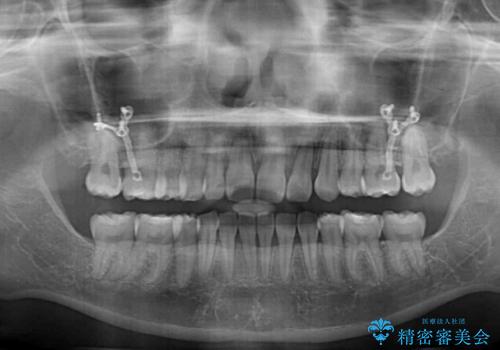

- 7ヶ月

出っ歯を抜歯矯正にて治療をしていらっしゃいましたが、抜歯スペースが少し残っていたため、閉じて歯列を仕上げていくこととしました。